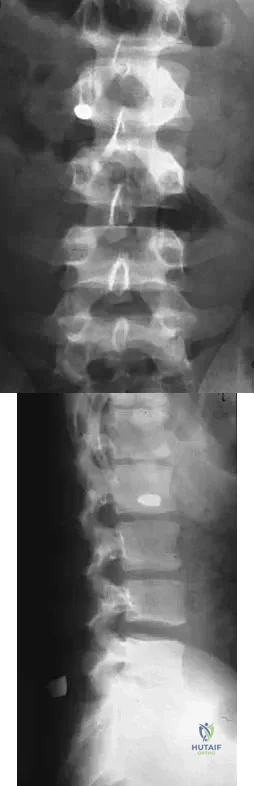

The condition shown in Figures 9a and 9b is most likely the result of